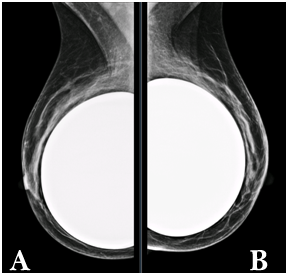

Figure 1 a) Right breast. b) Left breast. CC mammography views shows moderately dense fibroglandular parenchyma (pattern b ACR).

Figure 2 a) Right breast. b) Left breast. MLO views shows moderately dense fibroglandular parenchyma (pattern b ACR) with predominance in the upper quadrants. Retropectoral breast implants with preserved morphology.